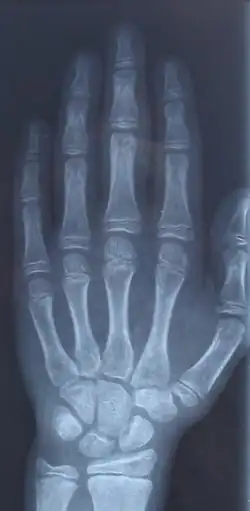

Kościec kciuka człowieka składa się z dwóch paliczków. Na pozostałe palce ręki składają się po trzy paliczki.

Rodzaje paliczków:

- paliczek bliższy (phalanx proximalis)

- paliczek środkowy (phalanx media)

- paliczek dalszy (phalanx distalis)